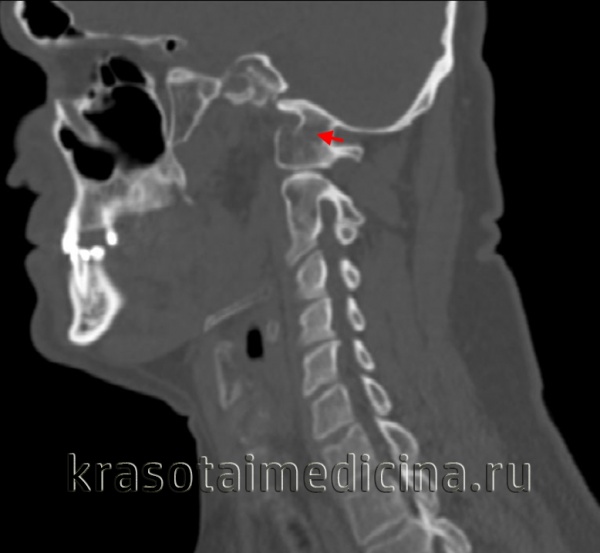

(Слева) КТ, фронтальный срез: расширение суставных щелей атланто-затылочных суставов (АЗС). Небольшие костные фрагменты представляют собой отрывные переломы нижне-медиального края мыщелков затылочной кости. Переломы в области прикрепления связок эквиваленты разрыву этих связок и только усиливают выраженность нестабильности КВС.

(Слева) Этот сагиттальный КТ-срез иллюстрирует передний подвывих мыщелка затылочной кости относительно С1. Видны свободно лежащие небольшие фрагменты мыщелка.